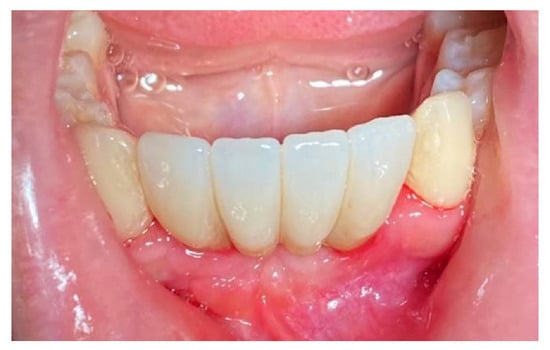

The patient was prosthetically rehabilitated with additional implants positioned in 4.2 and 3.2 (post-extractive). In this case, we also noted how soft tissues surrounding the regenerated site were mature and stable (Figure 18).

Figure 18.

Prosthetic finalization of the case and mucose quality.